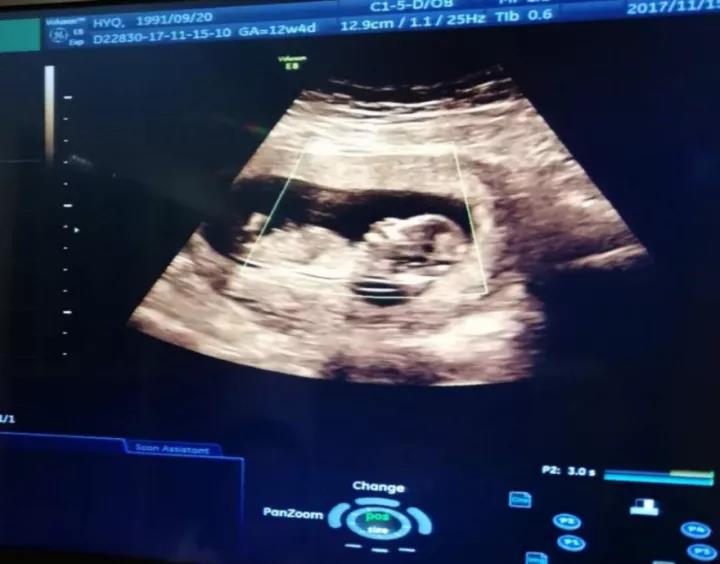

这个父亲节,我想手动”拍一拍“爸爸第一次,『穿越时空』见到你,超声影像中的你,像个小ET>>>在线客服